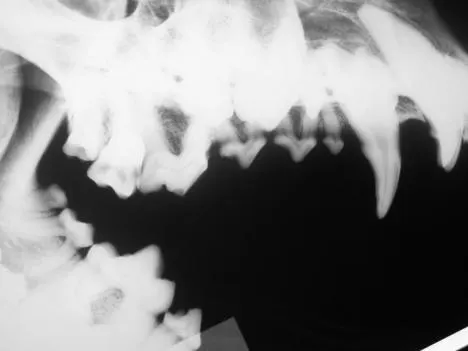

It is less convenient and more technically difficult to obtain high-quality dental images with traditional radiographic techniques. The radiograph machine is usually distant from the dental operatory, making it necessary to move the patient to obtain radiographs. Positioning is more difficult because the tube head is stationary. The need for extraoral film placement increases the difficulty of avoiding overlapping of structures. Dental films placed intraorally can be used with a standard radiographic machine to help with some of these problems; however, the practitioner wishing to incorporate dental radiology into his or her practice is advised to invest in a dedicated dental unit.

Skulls were used for these images. Dental images were obtained with a digital sensor; the traditional radiographs were taken using extraoral technique with a standard radiographic machine.

A lateral radiograph of a dog's skull shows the upper and lower jaw with clearly defined teeth and roots. The image highlights dental structures, including potential abnormalities such as tooth alignment and bone density.